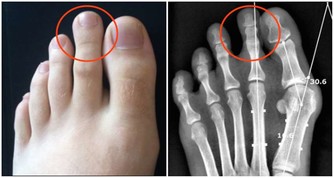

▼7. 杵狀指甲

亦稱作鼓棰指,即手指末端增生、肥厚,這可能是完全無害或源自遺傳,但如果是指甲突然開始軟化並大小不一,那代表你血液裡的含氧量低。此外,杵狀指甲有可能是肺部肝臟疾病、心臟病和炎症性腸疾病而引起的。